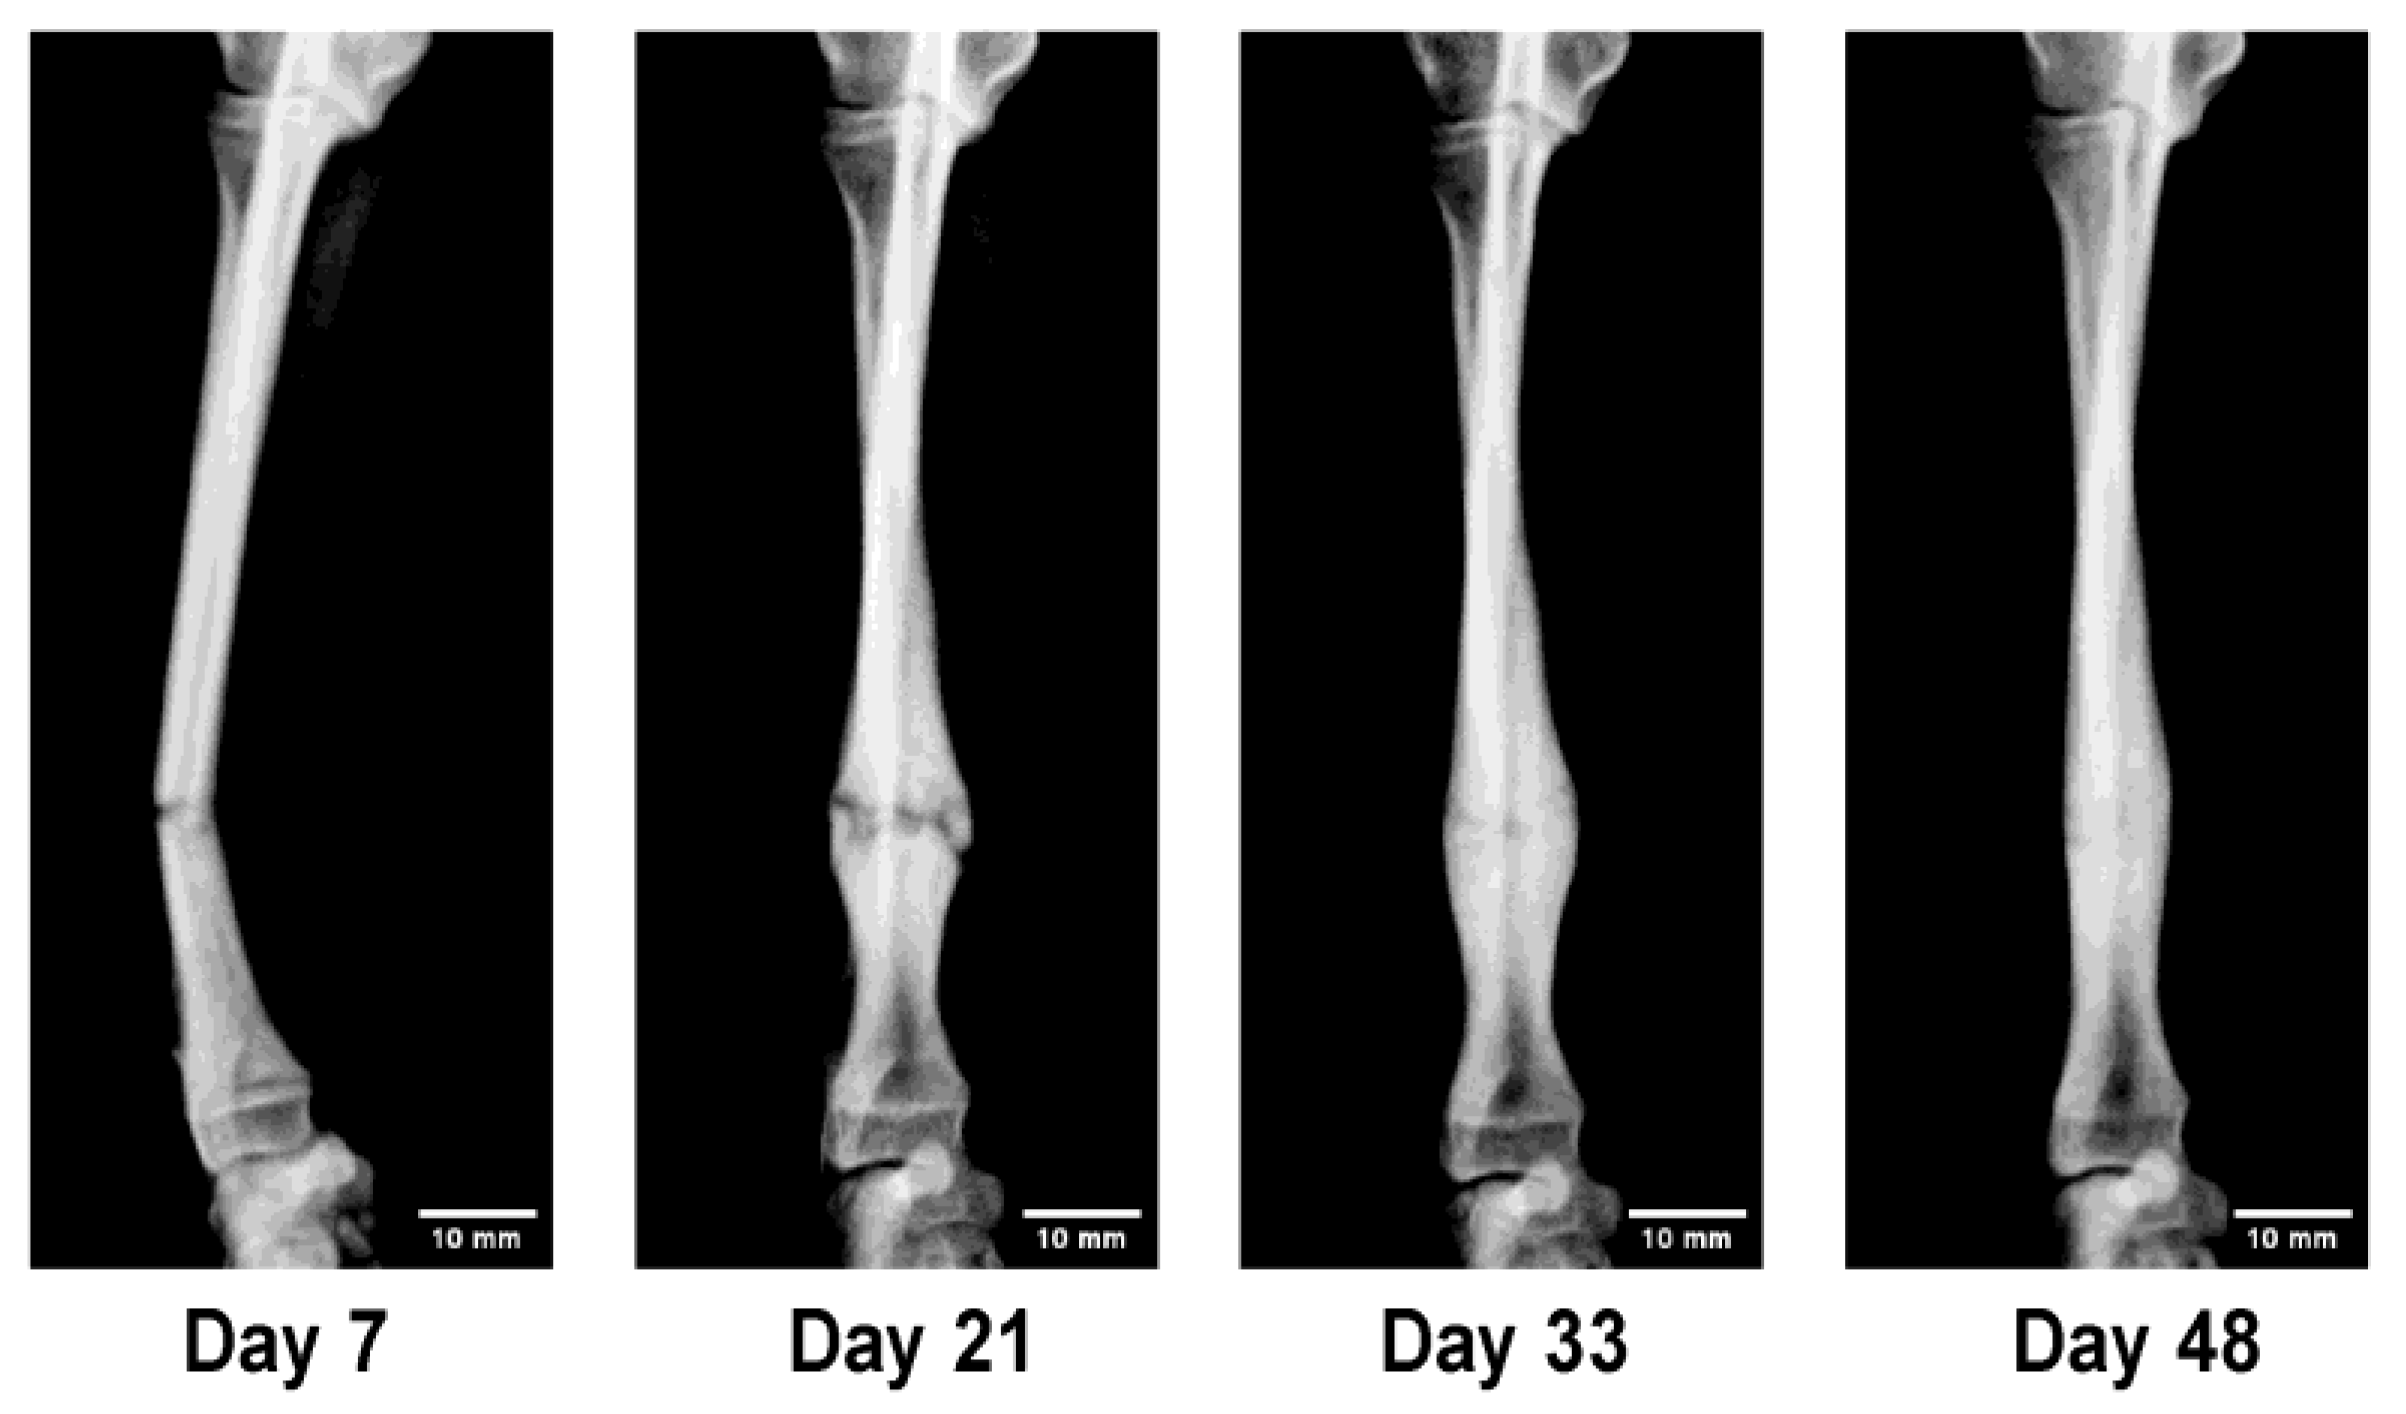

Figure 5.

Sequential radiographs showing rapid callus formation and remodeling in a juvenile dog (“Super-Healing”). Intensive callus proliferation and early bridging were observed within two weeks, indicating highly active osteogenesis under functional loading. This process reflects the intrinsic regenerative potential of young bone, providing a clinical in vivo model that parallels key concepts of regenerative medicine. (A) Day 7 after injury: fracture line remained distinct. (B) Day 21: marked increase in radial diameter due to callus formation. (C) Day 33: bridging callus confirmed; cast removed. (D) Day 48: remodeling with cortical thinning and increased density.

Figure 5. In a 5 month-old Toy Poodle treated with the 3D cast, active callus formation rapidly bridged the growth plate during the early healing phase. Two weeks after cast application, the bone diameter had increased to more than twice its original size, followed by gradual remodeling toward normal morphology. This markedly accelerated healing response, characterized by vigorous callus proliferation and early structural reconstruction, was defined in this study as “Super-Healing.”